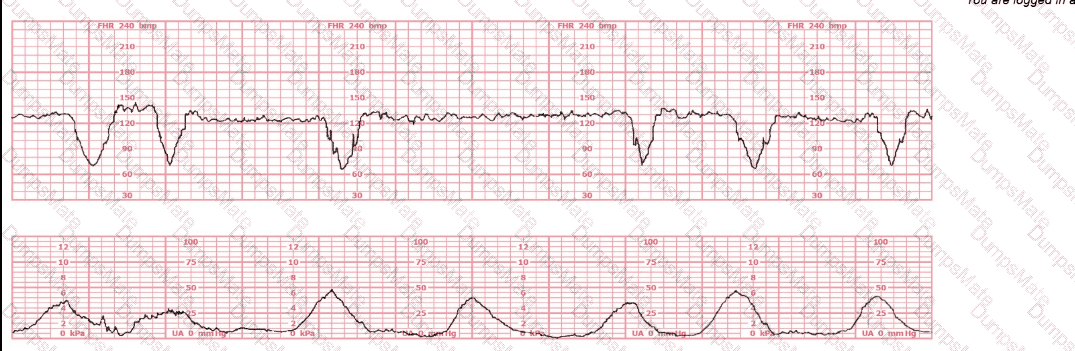

A woman at 38-weeks gestation is admitted to labor and delivery following a fall down the stairs three hours ago. She started feeling contractions in the ambulance. The fetal heart rate tracing shown is on initial evaluation and represents 25 minutes. This tracing is most consistent with a

EFM Question 27